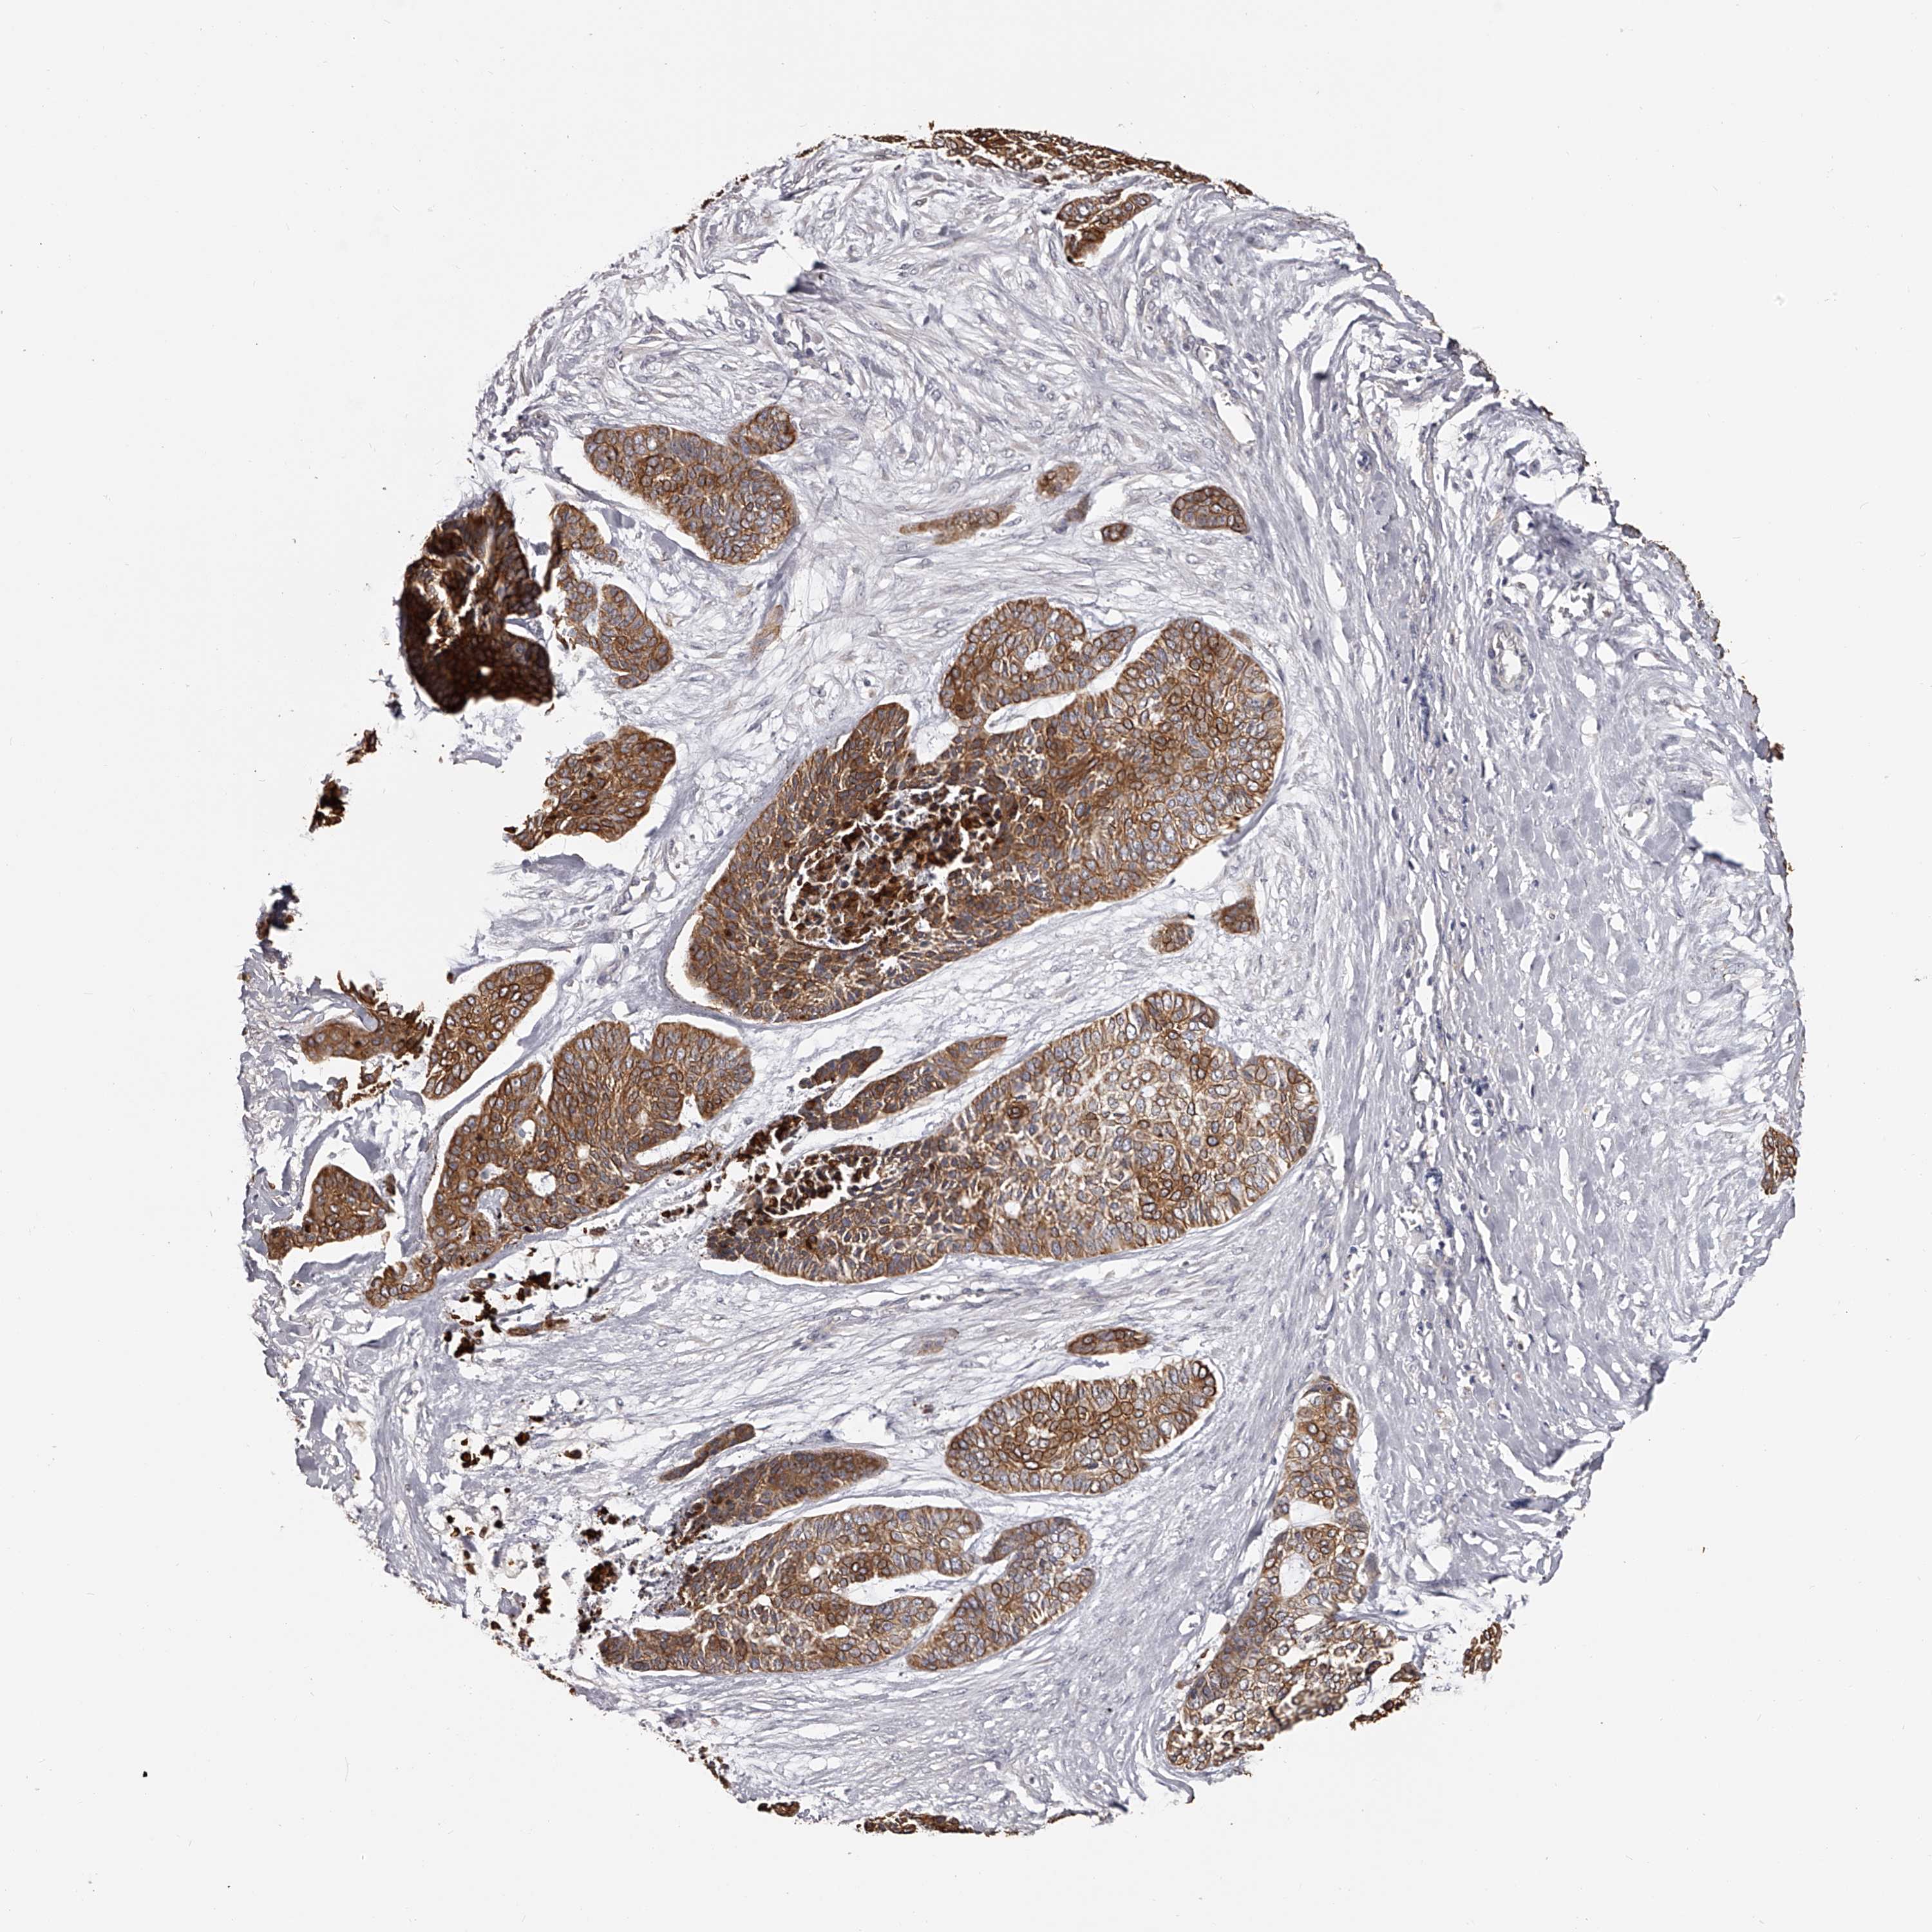

SKIN CANCER - Protein expressioni

A mouse-over function shows sample information and annotation data. Click on an image to view it in a full screen mode. Samples can be filtered based on level of antibody staining by selecting one or several of the following categories: high, medium, low and not detected. The assay and annotation is described here.

Antibody staining in the annotated cell types in the current human tissue is reported as not detected, low, medium, or high, based on conventional immunohistochemistry profiling in selected tissues. This score is based on the combination of the staining intensity and fraction of stained cells.

Each image is clickable and will lead to virtual microscopy that enables deeper exploration of all samples and also displays staining intensity scores, fraction scores and subcellular localization as well as patient and tissue information for each sample.

Antibody CAB010907

Medium

Moderate

75%-25%

Cytoplasmic/membranous

Squamous cell carcinoma, metastatic, NOS